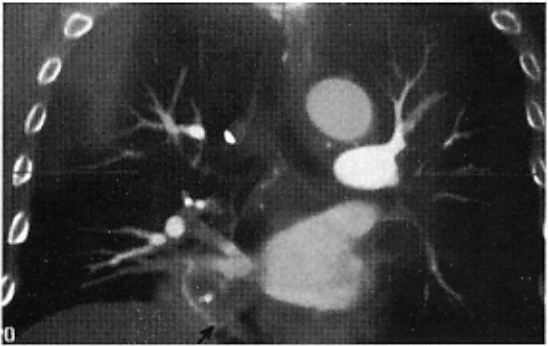

胸部CT+肺静脉成像:右下肺心缘旁团块状阴影,形态不规则,边界不清楚,最大径约3cm;增强后边缘强化,中央区无强化,与右下肺静脉关系密切(图)。支气管通畅,纵隔淋巴结无肿大。

图:胸部CT+肺静脉成像(上图为平扫,下图为增强),示右下肺心缘旁团块状阴影(箭头所示)与右下肺 静脉关系密切。